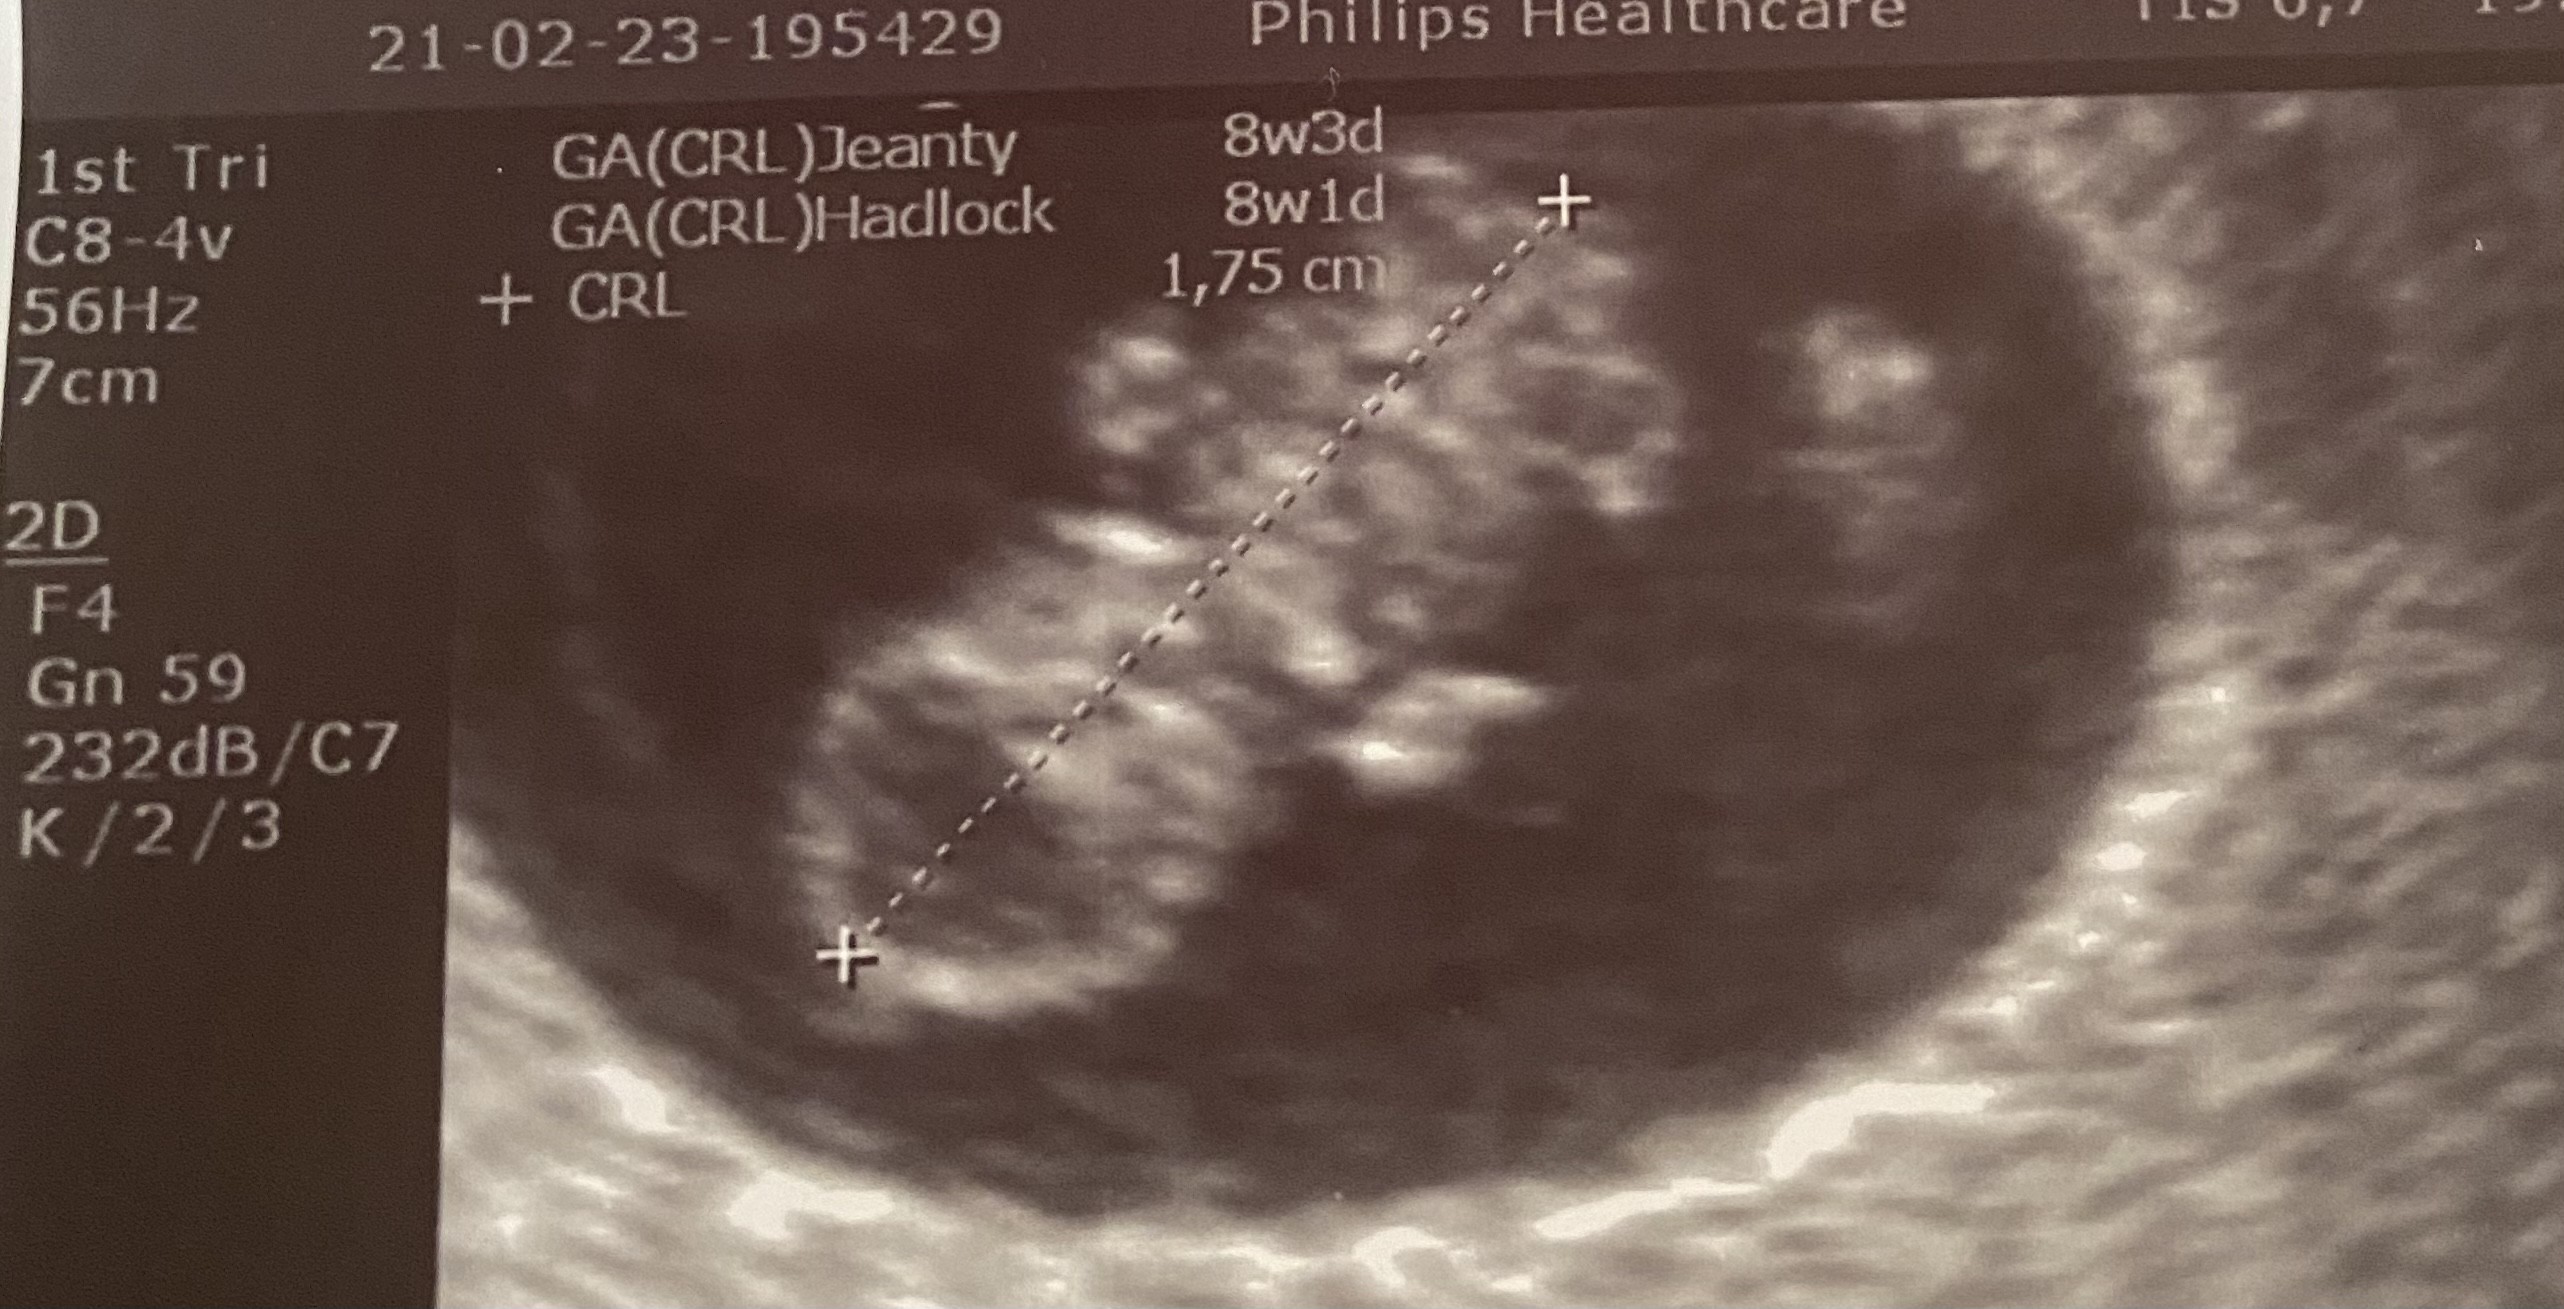

ciesze sie razem z wami z tych zdjęć usg,sama się nie mogę doczekać na swoje❤️. Na dzisiaj mam zmartwienie bo zlecialam ze schodów zlecialam dokładnie 13 schodow z góry na dół glowa obita prawa ręka obita i plecy obite mam tylko nadzieje ze nic się z moja fasolka nie stało bo bym nigdy w życiu sobie tego nie wybaczyla😭😭😭